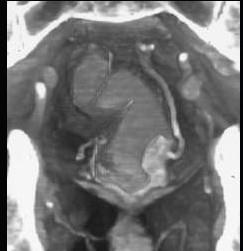

男,50岁,血便,大便形状改变,CT如图,应考虑为 ( )A、直肠腺瘤B、直肠淋巴瘤C、直肠内粪便D、直肠癌E、直肠息肉

问题 男,50岁,血便,大便形状改变,CT如图,应考虑为 ( )

选项 A、直肠腺瘤 B、直肠淋巴瘤 C、直肠内粪便 D、直肠癌 E、直肠息肉

答案 D